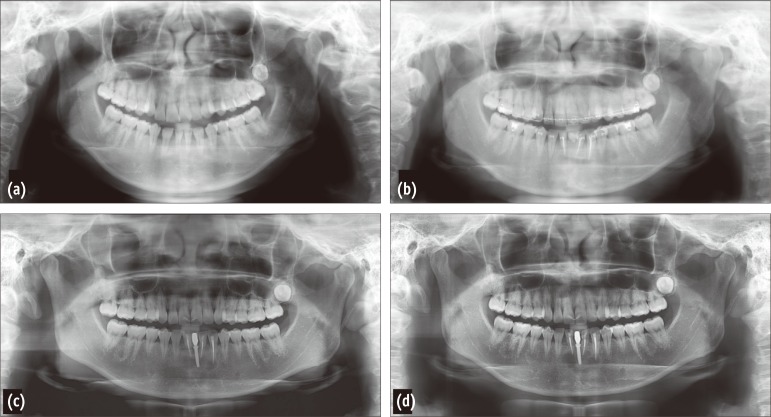

In 2009, a 30-year-old woman was referred to our institution for the evaluation and further treatment of the persistent lesions after root canal treatment of the mandibular anterior teeth (#32, 33, and 42) at a private dental clinic. The patient's medical history was unremarkable. The patient had visited the private dental clinic because of aesthetic concerns caused by congenitally missing mandibular anterior teeth (#31, and 41). The patient decided to receive an orthodontic treatment for teeth alignment and an implant surgery in the missing space. During orthodontic procedure, apical radiolucencies were detected and root canal therapies on those three teeth (#32, 33, and 42) were performed by her previous dentist. Based on the patient's report, she had received endodontic treatments because the dentist had suspected periapical pathosis due to the increased orthodontic force on the treated teeth. However, according to the previous dentist's referring notes, all of the teeth were vital at the time of treatment. On comparing a 4-year series of panoramic radiographs taken from 2005 to 2008, the previous dentist had observed that the apical radiolucencies on these teeth appeared to enlarge (Figures 1a - 1d). The dentist was concerned about the persistent periapical pathosis and referred to our institution for apicoectomies of the affected teeth. Panoramic radiographs obtained in 2007 and 2008 showed additional radiolucencies in the apical area of the mandibular right second premolar and the first molar as well as the left first premolar (Figures 1c and 1d).

Figure 1

A series of panoramic radiographs obtained during a previous dental consultation. (a) A panoramic radiograph obtained in February, 2005 (4 years before the initial visit to our institution) when the patient's dentist initiated orthodontic treatment. Slight periapical radiolucency on #32, 33, and 42 was detected; (b) A panoramic radiograph obtained in October, 2005 when the root canal therapies were performed on #32, 33, and 42; (c) A panoramic radiograph obtained in 2007; (d) A panoramic radiograph obtained in 2008. Compared with the radiographs in 2005, the size of the lesion in the mandibular incisors increased, and a mixed radiopaque and radiolucent area was clearly distinguishable in the apical areas of the right first molar, right second molar, and left first molar.

Figure 1 A series of panoramic radiographs obtained during a previous dental consultation. (a) A panoramic radiograph obtained in February, 2005 (4 years before the initial visit to our institution) when the patient's dentist initiated orthodontic treatment. Slight periapical radiolucency on #32, 33, and 42 was detected; (b) A panoramic radiograph obtained in October, 2005 when the root canal therapies were performed on #32, 33, and 42; (c) A panoramic radiograph obtained in 2007; (d) A panoramic radiograph obtained in 2008. Compared with the radiographs in 2005, the size of the lesion in the mandibular incisors increased, and a mixed radiopaque and radiolucent area was clearly distinguishable in the apical areas of the right first molar, right second molar, and left first molar.